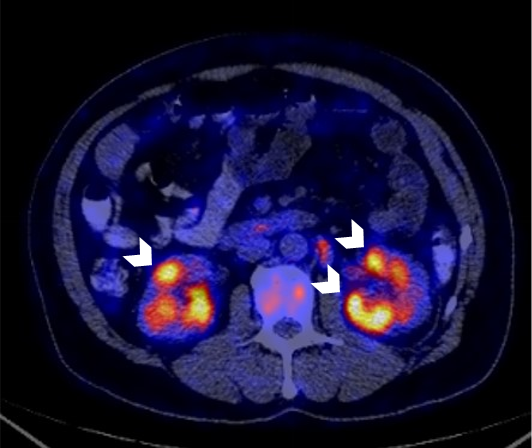

Metastatic neuroendocrine tumor of the small intestine: 219 MBq Ga-68 DOTA-TATE PET/CT imaging Fig. 1: NET with suspected primary of the small intestine Focal SSR uptake of the small intestine in the left middle abdomen without a pathologic correlate in the CT...